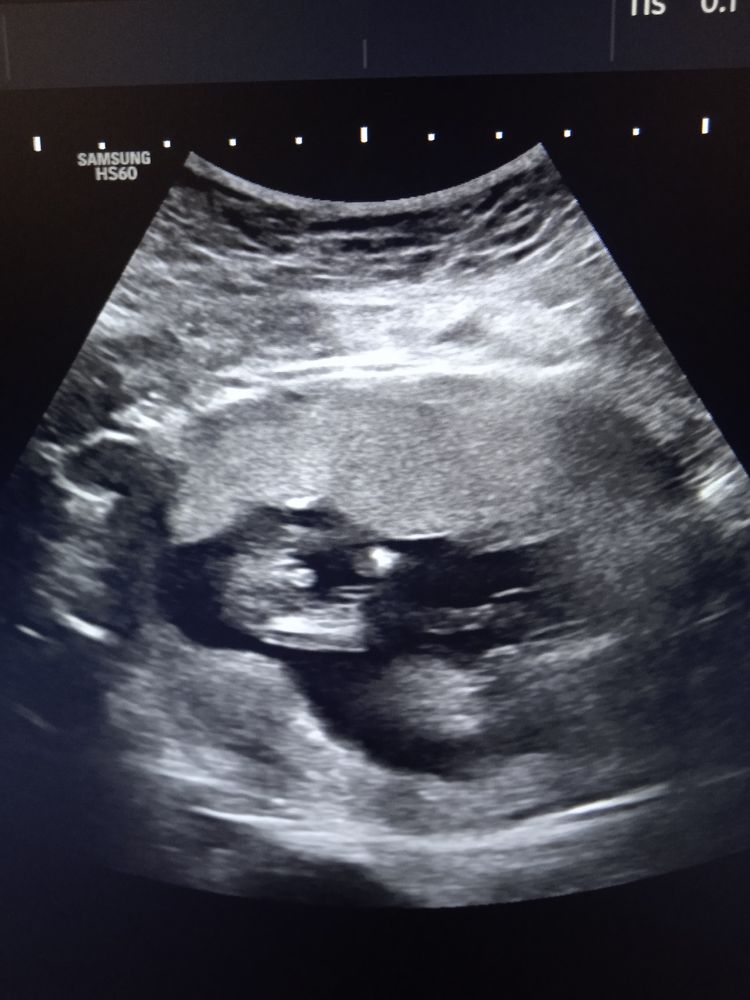

Мальчишка это))

Светлана, спасибо большое. Думаю, у вас тоже сынок 💕💪🏻 Когда девочка, там все по-другому, женский персик в миниатюре 🤭

В 11 недель по половому бугорку моя врач сразу сказала мальчик. В больнице на 16 неделе я видела именно такое изображение на экране узистка ещё раз подтвердила. Так и было.😎

Даша ЭдЛе, нам в 12.5 тоже сказали мальчик, а сегодня я че то тоже вроде вижу что торчит знатно, у девочек вроде всё более плоско,а чего то закрались сомнения🙈